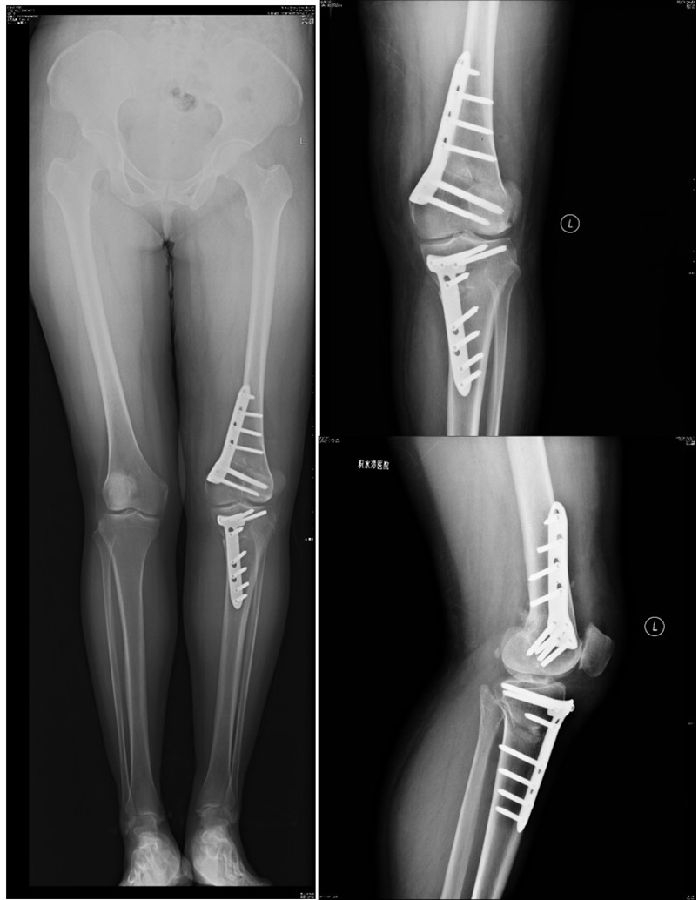

术后影像

患者二,女性,膝外翻,膝外侧疼痛。通过做畸形分析后发现,该患者同时存在股骨侧畸形、胫骨侧畸形和关节内畸形(LDFA=82°,MPTA=104°,JLCA=6°)。